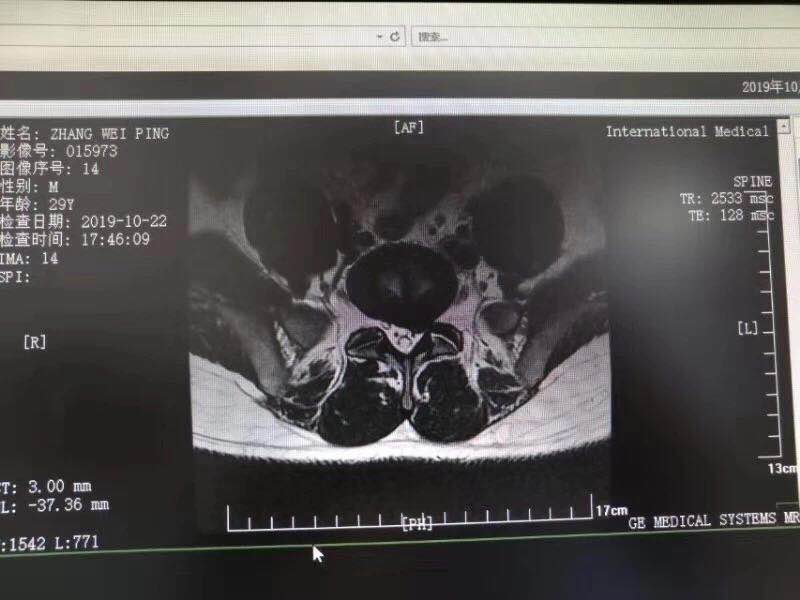

10月28日,西安國(guó)際醫(yī)學(xué)中心骨科醫(yī)院脊柱外科成功完成首臺(tái)椎間孔鏡手術(shù)。該手術(shù)結(jié)合加速康復(fù)外科(ERAS)理念的精細(xì)化管理和臨床路徑管理,采用微創(chuàng)的孔鏡技術(shù),為解除患者病痛。術(shù)后,患者左下肢放射痛即刻消失,第二天便下床活動(dòng)鍛煉,已……